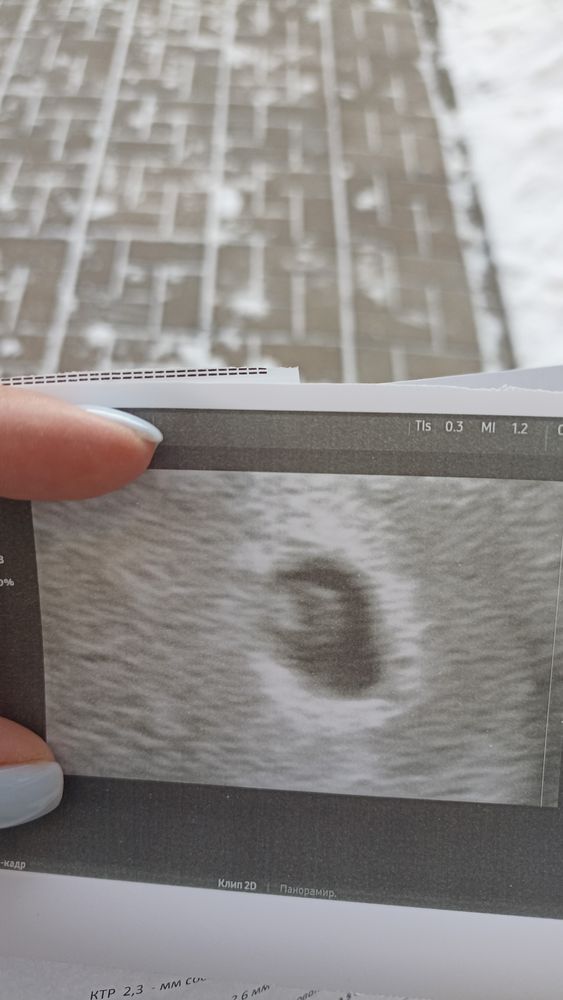

Первое УЗИ 21 ДПП😍

Я БЕРЕМЕННА !Сходила на первое УЗИ, не поверила своим глазам, там уже эмбриончик😍ктр 2.3 мм, жм 2.6))) и видно пульсацию, это было прекрасно 🔥

Маленькая белая точечка)